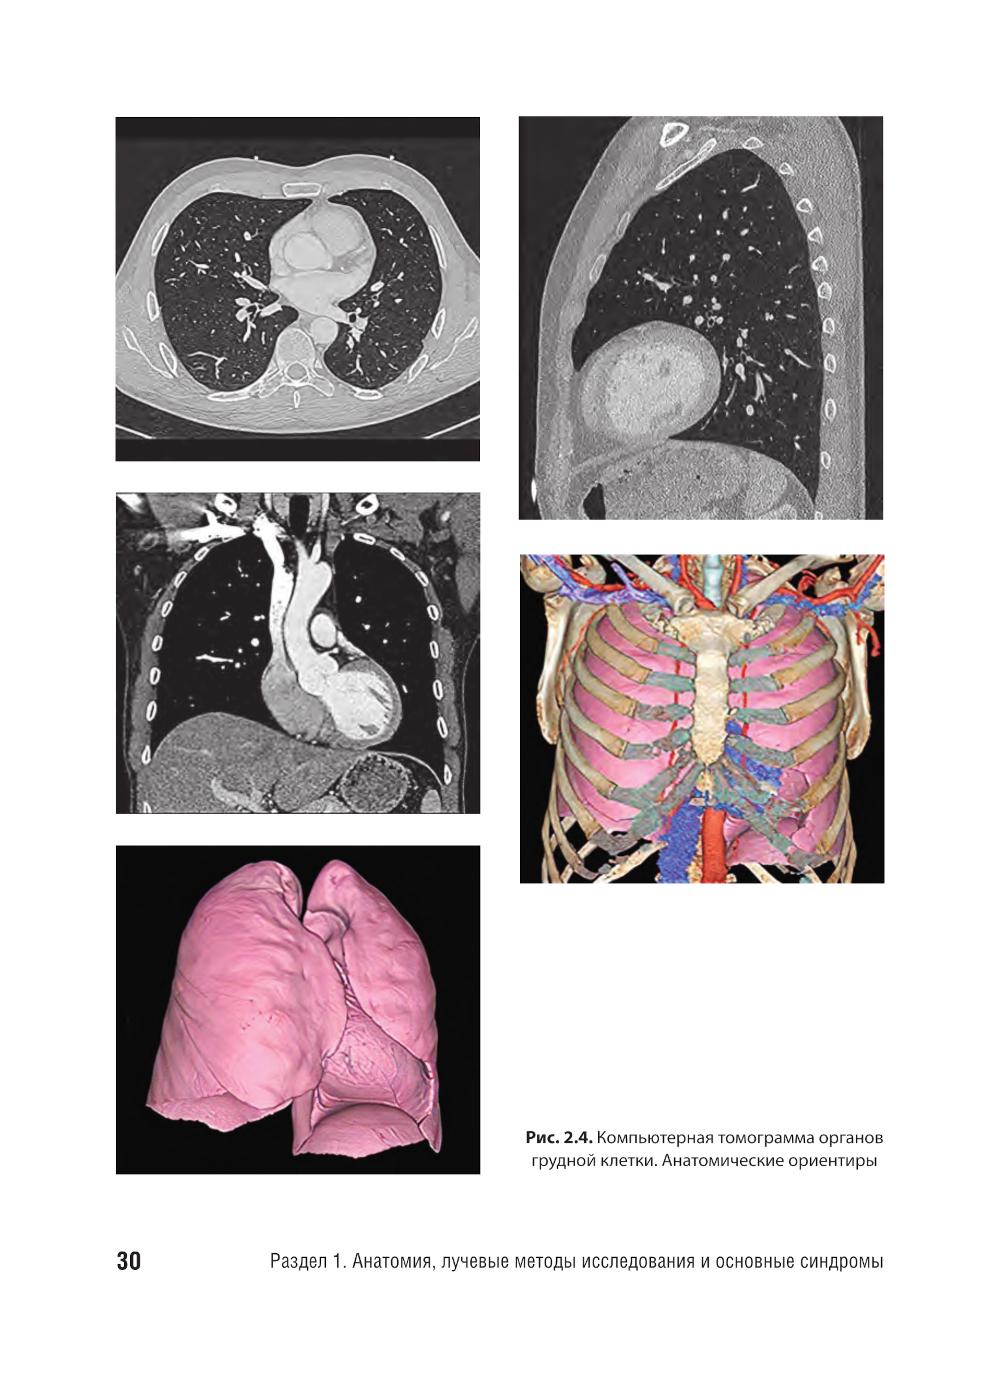

Практическое руководство представляет собой современное пособие, предназначенное для врачей-рентгенологов, пульмонологов, педиатров, терапевтов и других специалистов, занимающихся диагностикой и лечением заболеваний органов грудной клетки. В нем подробно рассмотрены методы лучевой диагностики, включая рентгенографию, компьютерную томографию (КТ). Приведены актуальные рекомендации по интерпретации лучевых изображений, основанные на последних достижениях медицинской науки и клинических рекомендациях. Руководство богато иллюстрировано высококачественными рентгенограммами, КТ-снимками, что делает его незаменимым инструментом для обучения и повышения квалификации специалистов. Издание адресовано как опытным врачам, так и студентам медицинских вузов, ординаторам и аспирантам, изучающим лучевую диагностику.| Издательство | ГЭОТАР-Медиа |